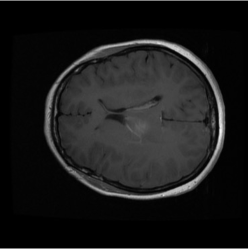

Numerous coreset selection works (Huang et al., 2023; Loshchilov and Hutter, 2015; Marion et al., 2023; Park et al., 2024; Paul et al., 2022; Xia et al., 2022; Yang et al., 2023a) have explored various criteria for identifying important data samples, including geometry distance (Sener and Savarese, 2017; Welling, 2009), uncertainty (Coleman et al., 2019), loss (Toneva et al., 2018; Paul et al., 2021), decision boundary (Ducoffe and Precioso, 2018; Margatina et al., 2021), and gradient matching (Mirzasoleiman et al., 2020). However, most of these methods have been validated mainly on natural image datasets, such as CIFAR-10, CIFAR-100 (Krizhevsky et al., 2009), and not extensively on medical datasets. The applicability of those methods for medical image datasets are under exploration, given the unique characteristics of medical images. Compared to natural image datasets, the intra-class variation and inter-class similarity of medical image datasets (Song et al., 2015) pose specific challenges to coreset selection. On the one hand, in medical imaging, samples within the same category can exhibit significant differences, making it difficult to capture consistent features for each class. This variation largely comes from the diversity in disease manifestation across patients and discrepancies in imaging conditions. On the other hand, the challenge of inter-class similarity arises when images representing different diseases exhibit similar visual characteristics. fig. 6 provides a more straightforward demonstration of this characteristic. These factors contribute to the complexity of medical image analysis and underscore the need for sophisticated coreset selection methods that can effectively address these challenges.

Despite the substantial progress, integrating deep learning into medical imaging is fraught with challenges (Ker et al., 2017). The effectiveness of DL in this context is largely dependent on the availability of large, well-annotated datasets tailored for specific tasks and reliant on advances in high-performance computing. The necessity for vast complex datasets introduces complications such as inconsistencies in data quality, arising from variations in imaging equipment and protocols. Moreover, the extensive volume of medical data demands significant computational resources, posing logistical challenges for efficient processing (Zhou et al., 2021). Additionally, the inherent heterogeneity of medical images, characterized by a multimodal probability distribution, complicates the model training process by requiring algorithms capable of handling diverse visual features and patterns within the data. Another issue is the inter-class similarity and intra-class variation, as depicted in fig. 6, where different diseases may appear similar, and the same disease may present differently across patients.